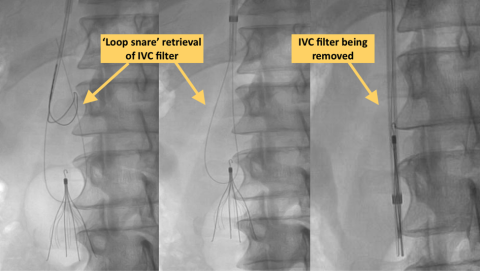

At UCLA, the expert team of Interventional Radiology physicians employ a wide variety of advanced techniques to remove the most challenging IVC filters, even ones that have been embedded for many years, or where attempts at removal at other centers have failed before. UCLA is a “quaternary hospital” referral center, receiving referrals for such difficult cases from centers around the country and even abroad. These include the use of forceps, laser retrieval, a variety of ‘loop snare” and balloon assisted techniques. Most patients will go home the same date after filter removal.